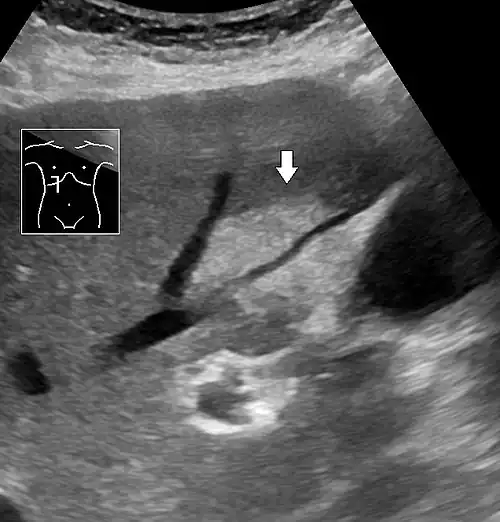

Abdominal ultrasonography with the liver and kidney side by side (left image) may give a false impression of hyperechogenic liver, so it's preferably done with the organ borders facing the ultrasound probe (right image, of the same case). -